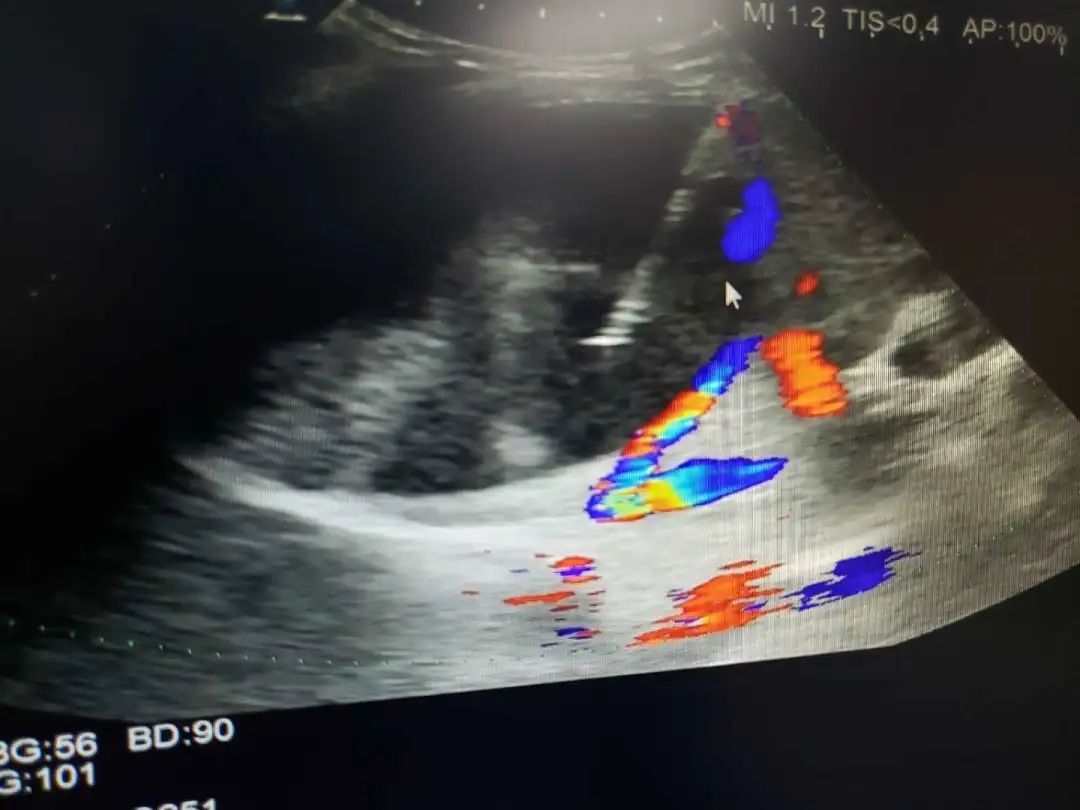

超声引导下肿瘤消融治疗是在实时超声的监视引导下应用专门的治疗针,达到不开刀、对体内的肿瘤原位灭活的一门新技术,其中肝癌经皮微波凝固治疗处国际领先地位。

微波消融治疗肝癌可采用经皮穿刺、开腹手术术中消融或经腹腔镜引导几种方式,超声引导下准确地摆放微波辐射电极,保证凝固坏死区完全覆盖整个肿瘤,达到完全灭活肿瘤。对于小于3厘米的肝癌,射频、微波消融治疗技术成熟,已经取得和手术相同的临床效果,但微创、安全、经济、痛苦小是手术方法无法替代的,尤其是无法耐受手术及复发和转移的肝癌。